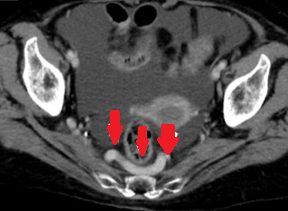

CT κοιλίας. Κόκκινο βέλος — Τυφλίτιδα. Σημαντική πάχυνση τοιχώματος τυφλού (Ευγενική παραχώρηση Dr. V. Penopoulos)